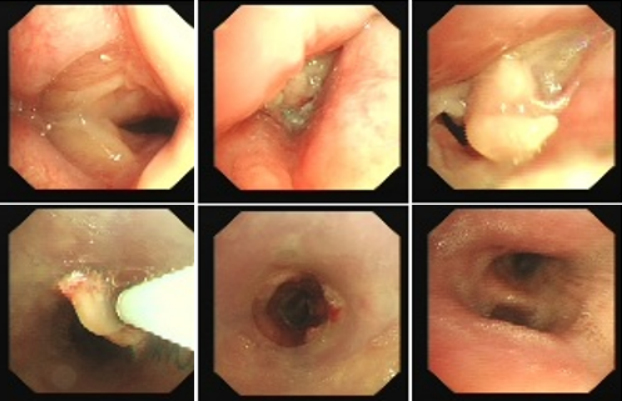

良性中心气道狭窄分为结构性和动力性(6种类型),结构性狭窄包括:管腔内生长(1型),外源性压迫(2型),瘢痕孪缩(3型),扭曲变形(4型);动力性狭窄包括:气道膜部向内膨出(5型),气道软化(6型)。对于动力性狭窄,应考虑用力呼气时的状态,通过操作者的判断,定出最合适、最接近的狭窄程度。治疗方法的制定不仅与气道狭窄程度和长度有关,还与是否存在狭窄过渡段有关。狭窄长度的计算应包括过渡区域。良性气道狭窄形态学分类的诊断方法应通过支气管镜所见及放射学检查来确定。每一个狭窄都可以用4个数字来表示,分别代表部位、类型、狭窄程度、狭窄长度。如:1344代表声门下瘢痕性挛缩性狭窄、狭窄程度>75%、狭窄长度>5 cm,这是一种非常难以处理的良性气道狭窄;2311代表气管瘢痕性蹼状网眼狭窄、狭窄程度<25%、狭窄长度<1 cm,这是一种比较容易处理的良性气道狭窄。热消融技术(APC、电凝、激光)是治疗增生性气道腔内病变(如良性肿瘤和单纯肉芽)的简单、快速的方法。但在治疗瘢痕狭窄病变时,其本身可对气道造成更重、更大范围的损伤,引起更为严重的肉芽组织增生和瘢痕形成,从而导致复发率高,且治疗次数的增加可导致狭窄病变范围增大并最终破坏软骨,导致气道塌陷,使患者彻底失去治愈的机会。电凝和APC仅适合管腔内生长的1型良性中心气道狭窄,并不适合其他类型良性中心气道狭窄的治疗。即便如此,基底部的处理也应避免使用此类治疗方法。针形电刀与气道黏膜接触面极小,不会造成损伤面扩大,瘢痕性气道狭窄的治疗宜选用针形电刀进行切割、松解。因激光也有切割的作用,因此也可选用激光治疗,钬激光、铥激光控制烧灼深度最浅可达0.4 mm,因此更适合良性瘢痕增生性气道狭窄的治疗。冷冻治疗分为冷冻切除(简称冻切,cryoextraction)及冷冻消融(简称冻融,cryoablation)。对于腔内生长的病变可采用冻切治疗,由于容易出血,其安全性不如热消融技术。对于瘢痕病变,冻切技术无法实施,则采用冻融治疗,冻融治疗不促进肉芽组织增生。与热消融相比,冷冻不易导致软骨损伤。通常在热消融治疗接近气道壁时或球囊扩张后采用冻融治疗处理剩余病变,有利于减轻瘢痕再狭窄发生的速度与程度。严重气道狭窄在开通气道前不要使用冻融,因其可引起气道水肿,加重气道狭窄,从而导致窒息。因此,冻融治疗后肺部体征监测及气管镜复查十分重要。机械扩张技术包括球囊扩张和硬质支气管镜扩张,并发症有气道撕裂、再狭窄、出血。(1)球囊扩张:是治疗瘢痕性气道狭窄最主要的技术,其优势是患者治疗后无明显的狭窄段延长,狭窄复发时再狭窄的程度比热消融治疗后轻得多,有利于维持气道复张的疗效。对气管黏膜损伤小,可以在软镜下应用,但需要中断通气。对于挛缩、韧性较强的瘢痕,可先用针形电刀进行切割以松解瘢痕;避免直接暴力球囊扩张,导致气道膜部的撕裂伤。(2)硬质支气管镜扩张:其优势是扩张时不需要中断通气,安全性更好。针对瘢痕肉芽组织增生导致介入治疗后的气道再狭窄,可采用气道狭窄部位局部应用药物的方法抑制瘢痕肉芽组织增生。介入治疗后气道再狭窄可选择的治疗药物有:糖皮质激素、丝裂霉素C、曲尼斯特、紫杉醇等。通过直接植入放射性物质(最常用铱-192)或经过可弯曲支气管镜近距离照射气道瘢痕肉芽组织,促使成纤维细胞凋亡。气道支架置入首选硅酮支架,禁用金属裸支架。支架治疗应作为良性气道狭窄最后选择的治疗技术,启动气道支架治疗的指征:①应用前述各种治疗方法疗效不佳,不能维持气道通畅;②在确定外科手术前临时放置;③外压性气道狭窄;④气道软化、塌陷且无法或不准备行外科手术治疗。病例1:17岁,女性,骨折术后肺炎插管,拔管后(2月14日)气道明显狭窄(图3)。2月15日评估:HR 113次/min,R 24次/min,静息下SpO2 97%(FiO2 50%),咳嗽及说话后喘鸣,有阵发性血氧下降。会诊后拟行急诊介入治疗。2月15日无痛气管镜示:声门下腔黄色及乳白色膜状坏死物,气管上段大量黄色坏死物并管腔重度阻塞,仅见小孔,以冷冻法清除坏死物后管腔通畅(图4)。术后气促明显改善,无需吸氧。病例2:77岁,女性,呼吸困难2个月,加重3天,于2023年12月2日入院(2023年9月气管插管,插管后20余天后拔管)。入院当天查体:HR 125次/min,R 30次/min,静息下SpO2 96%(高流量FiO2 30%),PaCO2 56 mmHg。患者术前影像如图5所示。12月3日查体:HR 140次/min,R 35次/min,BP 190/90 mmHg,SpO2 68%~75%(FiO2 100%),躁动不安,急查血气分析:PaCO2 89 mmHg。紧急床旁无创通气支持下气管镜:气管上段狭窄80%以上,较多黄白黏稠分泌物在狭窄口随呼吸摆动,予抽吸后SpO2升至98%,见狭窄处直径约3 mm,外径5.2 mm,软镜无法进入,遂置入导丝,10#球囊扩张多次,狭窄部位增宽,外径4 mm气管镜引导6.0号气管导管经口插管成功(图6)。插管后患者HR 98次/min,复查血气分析示PaCO2 41 mmHg,氧合指数300 mmHg以上。12月4日气管镜示:右鼻旁路进镜,缓慢退气管导管至声门,距声门3 cm处狭窄,直径7 mm,予12#球囊扩张1 min,2次,未见出血,扩张后直径约12 mm,地塞米松局部保留,气管导管复位(图7)。12月5日拔除气管导管。12月6日气管镜示:气管上段瘢痕狭窄(管径10~12 mm),少许膜状坏死、未见肉芽,予以清除坏死物,7点、11点冻融,术毕注入地塞米松5 mg(图8)。12月13日气管镜示:气管上段瘢痕狭窄(管径12 mm左右),少许膜状坏死、未见肉芽,予以清除坏死物,7点、11点冻融,术毕注入地塞米松5 mg(图9)。